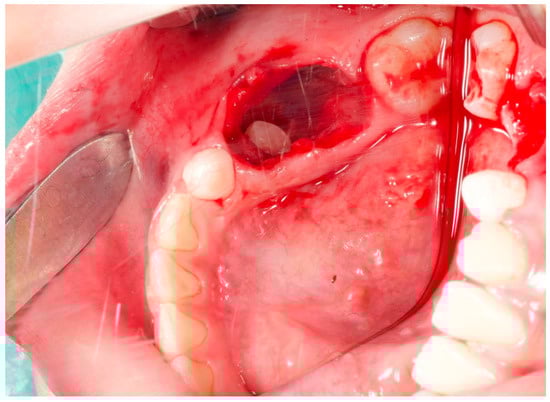

2. Case Report

3. Follow-Up and Outcomes